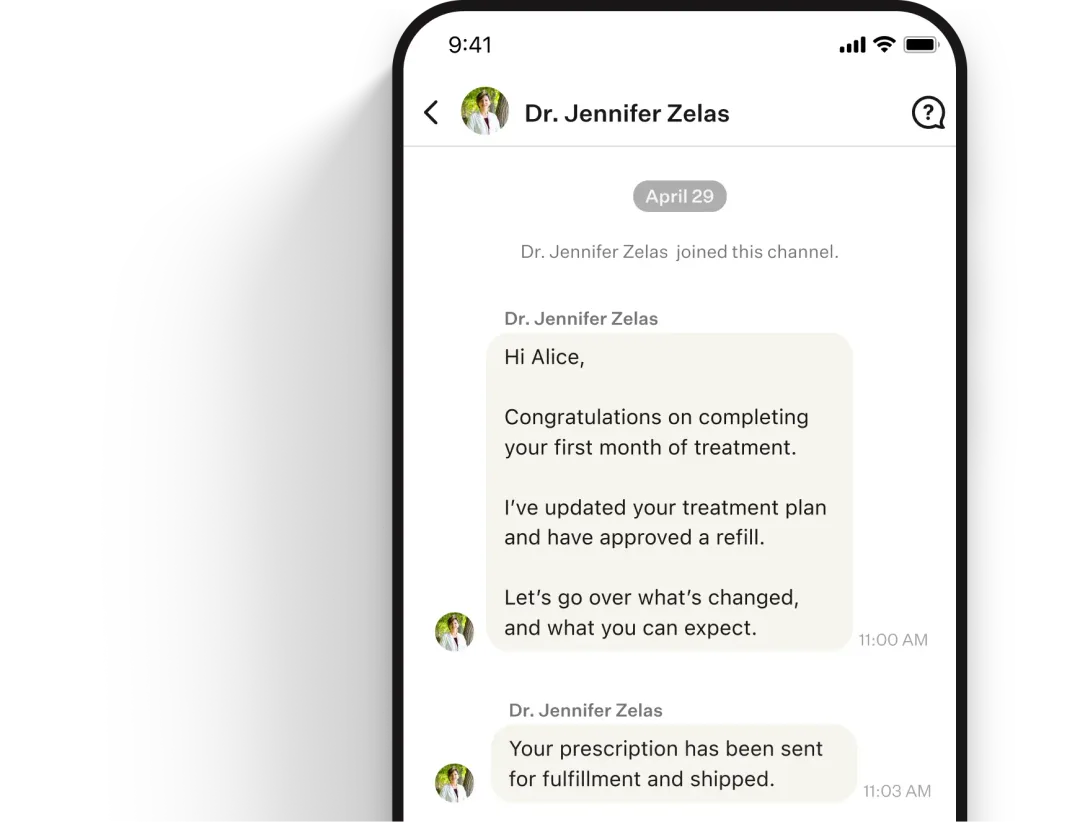

Consult with an expert clinician

A clinician will quickly evaluate your results and provide a prescription all online, if clinically appropriate.

Ongoing care and medication

Stay on track with unlimited access to your clinician and medication refills, where clinically appropriate.